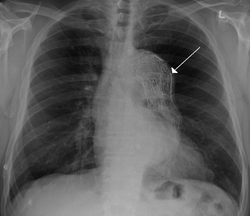

Thoracic aortic aneurysm with arrow marking the lateral border of the aorta